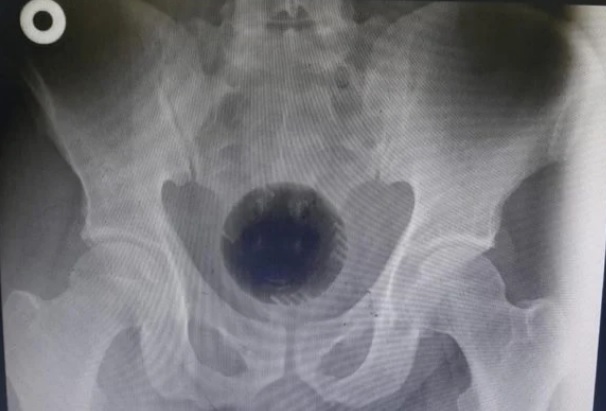

Paciente dá entrada na emergência com bola de 7 cm presa no ânus

Um homem de 51 anos chegou ao hospital na Jordânia precisando passar por uma cirurgia de emergência por um motivo pouco usual. Ele enfiou uma bola de 7 cm no fiofó. O material equivale a uma bola de tênis profissional e ficou preso no reto.

Os médicos tentaram retirar o material com um lubrificante, mas quando viram que não teria jeito, usaram uma espécie de furadeira introduzida pelo ânus para quebrar a bola em 3 pedaços.

“Infelizmente, o corpo estranho estava firmemente preso na pélvis, movendo a bola impactada para cima”, escreveram os médicos no artigo.